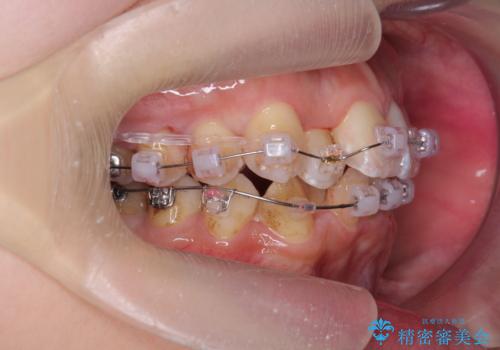

右下の臼歯が内側に倒れこみ、小臼歯部分はすれ違い咬合、大臼歯も反対咬合となっていました。

歯の大きさを計測したところ、下の歯がとても大きく、4本抜歯したとしても奥歯のかみ合わせを交互にするのが難しい状態でした。

この状態からうまく治療ができれば右下を頬側に起こすことができればある程度スペースが確保できそうでした。

下については、まずは動かして起こしてみて抜歯の本数は治療をすすめながら1本、右上下2本、上下左右4本の選択肢のうちどれかになるという方針としました。

初めから抜歯をしてしまうと戻れない為です。